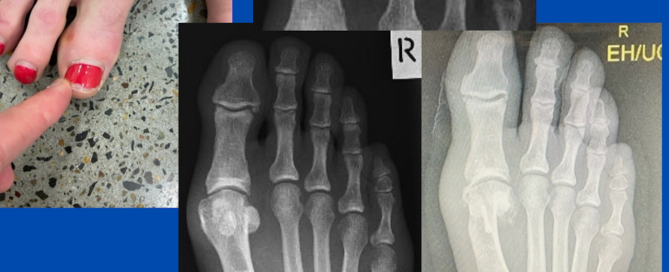

Nerve entrapment from early bunion formation

Blog's main page This lady presented with marked shooting pain in the right dorsal medial 1st MTPJ. She has endured this pain for approximately 12 months, with little relief from [...]